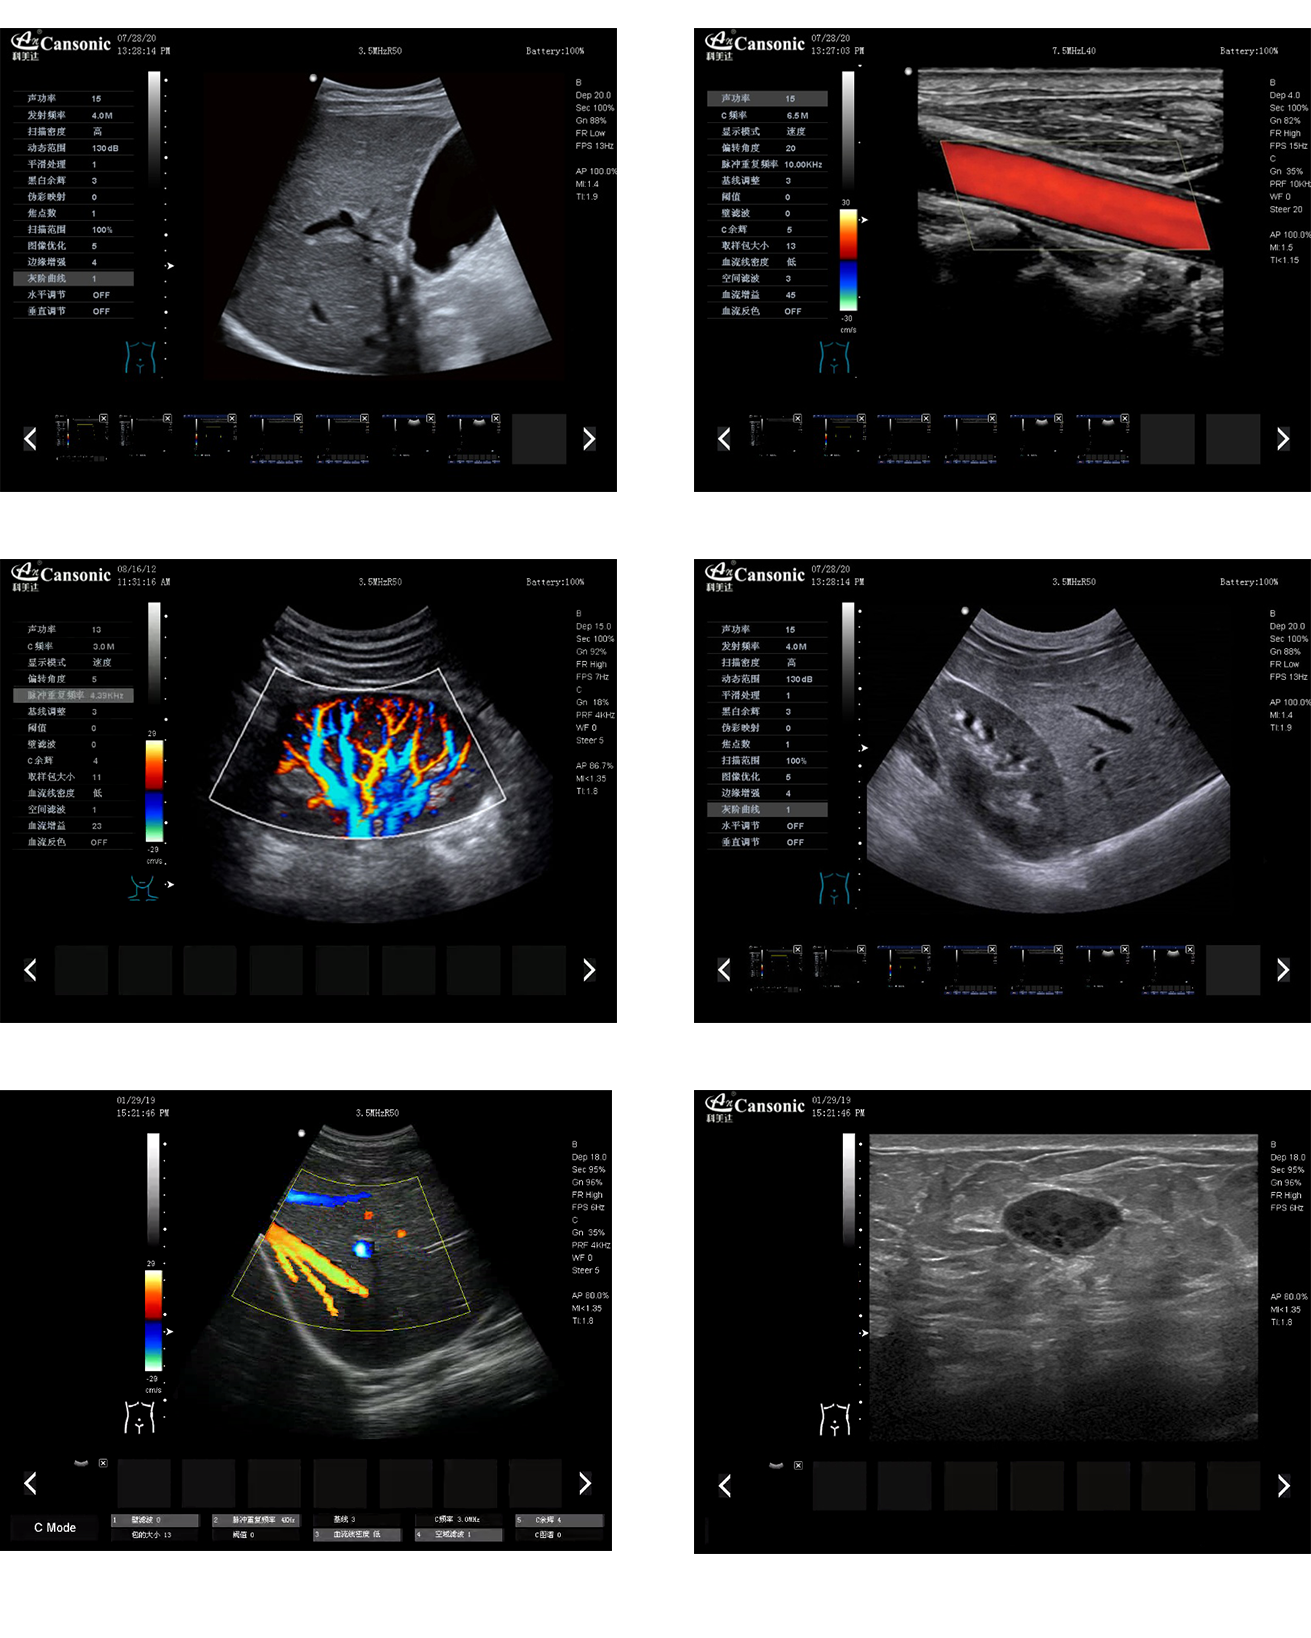

科美達K8圖像實例

1、全新一代便攜彩超,采用高端彩超技術,提供完整的臨床解決方案,適應各種臨床環境

2、圖像細膩,質量優異,同時性能穩定,每天能做大量檢查

3、選擇手動或自動包絡頻譜,一鍵顯示各種血流動力學數據

4、高分辨率灰階血流成像,明顯提升對微細血管的血流探測能力,對大血管管壁成像及管壁斑塊的診斷有著很大幫助